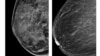

سونوگرافی به اندازه ماموگرافی برای تشخیص سرطان پستان مؤثر است

ماموگرام غالبا تفاوت بین بافت های فیبری سفید پستان و سلول های سفید غدد را در صورتی که این غدد سخت نشده باشند، تشخیص نمی‌دهد. اما اولترا ساند این تومورها را به رنگ خاکستری نشان می‌دهد، که تشخیص آنها را از بافت های سالم بدن میسر می‌کند.

ماموگرام با استفاده از اشعه ایکس و اولترا ساند با استفاده از امواج مافوق صوت انجام می‌شود.